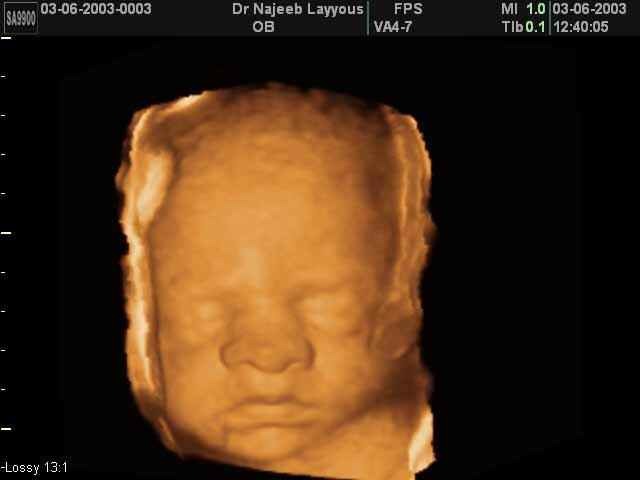

The baby is getting hair on eyelashes, scalp, and eyebrows appear.Organs are maturing, and the baby becomes more active. The mothers "baby bump" becomes more noticeable.She can feel slight fetal movements, and her posture may be affected.

-